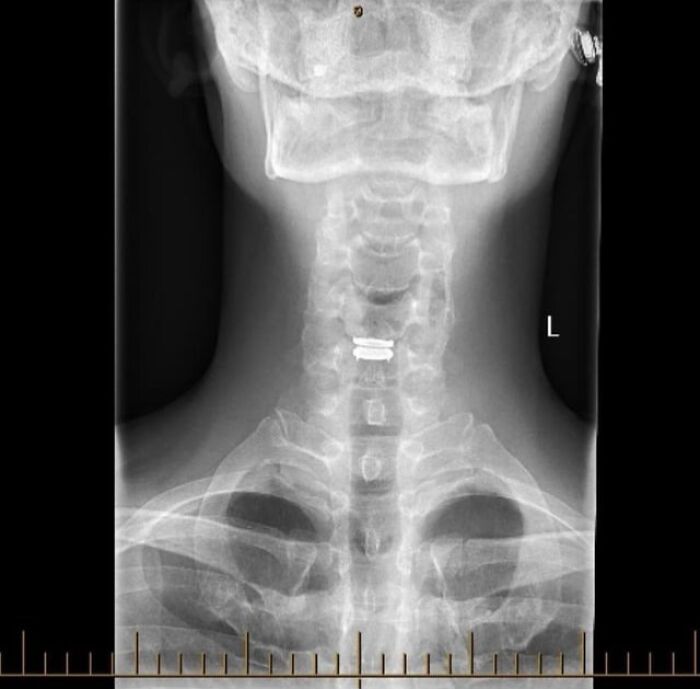

La comunidad médica de Reddit revela la gran cantidad de cosas que suceden tanto dentro como fuera de nosotros.

Desde la apariencia de nuestros cuerpos hasta el funcionamiento de nuestros órganos, están llenos de sorpresas. Algunas de las cosas que se comparten allí son poco comunes, como enfermedades o afecciones inusuales con las que la mayoría de nosotros no nos topamos normalmente.